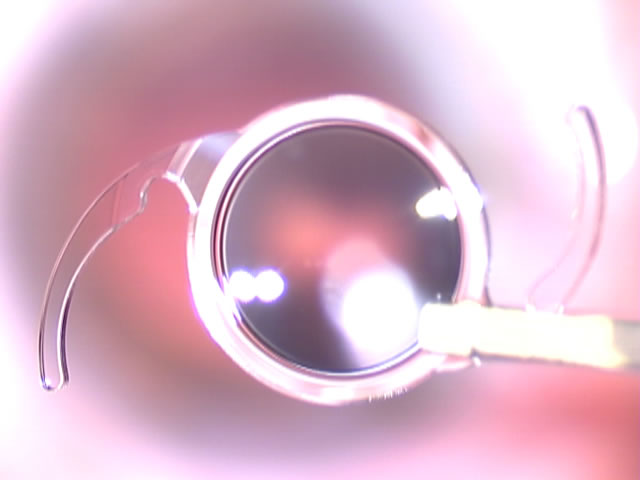

Presso il proprio studio di Gussago (Brescia), il dottor oculista Giovanni Coen esegue interventi di chirurgia refrattiva con impianto di lenti intraoculari asferiche Premium: una soluzione che permette la correzione dei difetti del cristallino (la seconda lente dell'occhio, situata internamente rispetto alla cornea) che, spesso anche per l'avanzare dell'età, perde la propria trasparenza causando una visione poco nitida e non definita. La microchirurgia del cristallino offre risultati eccellenti anche in presenza di cataratta e consente di eliminare difetti come la miopia, l'ipermetropia, la presbiopia e l'astigmatismo.

L'intervento consiste nella sostituzione, mediante laser, del cristallino danneggiato con lenti intraoculari artificiali mono o multifocali personalizzate, che garantiscono una visione perfettamente limpida, ad alto contrasto e priva di difetti. Il trattamento chirurgico è indolore anche nel post intervento, avviene tramite anestesia topica in gocce e permette l'immediata ripresa delle attività quotidiane in sole 24 ore.